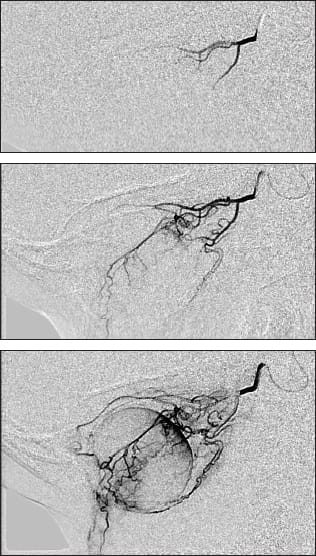

Figure 3. Superselective ophthalmic artery cannulation, followed by an angiogram showing vascular supply to the eye and focal delivery of chemotherapy.